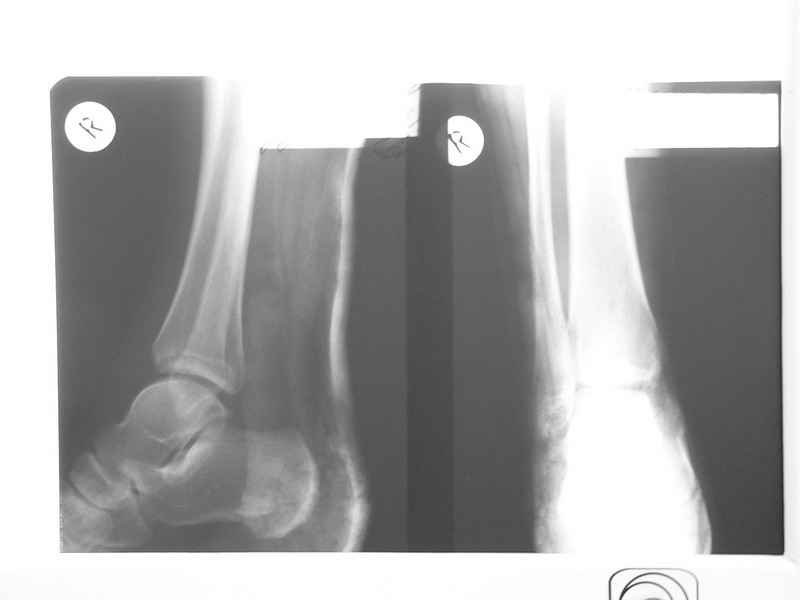

Re: Остеомиелит медиальной лодыжки

Совершенно верно был такой Пациент парень 29 лет. Только не 2 года а 4 года назад. Лечение растянулось на 2 этапа. На момент сообщения наложил окончатую гипсовую повязку, мазевые повязки, грануляции, закрыл свободной кожной пластикой. Через 2 месяца рана закрылась рубцом, гипс снял отправил на ЛФК. В течение года появлялся дважды - все ОК, нестабильности в суставе не было. Пациент работник УВД - его даже не комисовали. Обратился через 2 года после повторной травмы (опять мотоцикл) - открылся свищ в области медиальной лодыжки. Проведена операция - санация, рубец иссечен, пластика суральным лоскутом - состоятельная. Аппарат Илизарова на 2 месяца. Аппарат демонтировали опять ЛФК - Нестабильности в суставе нет, до сих пор трудится в органах... Опять подумывает о покупке мотоцикла.

К сожалению снимки нашел только после пластики. Р-гр где-то утерял посмотрю не работе.